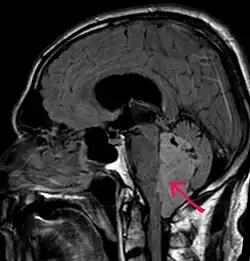

Wyściółczak – nowotwór glejowy ośrodkowego układu nerwowego, wywodzący się z tkanki wyścielającej światło komór mózgu i kanału środkowego rdzenia kręgowego (ependymy). Po raz pierwszy został opisany przez Percivala Baileya w 1924 roku[1].

Wyściółczak jest dobrze odgraniczoną od otoczenia, guzowatą zmianą wyrastającą do światła komór lub kanału środkowego rdzenia kręgowego. Zmiany wewnątrzczaszkowe zlokalizowane są zazwyczaj w komorze czwartej; mogą zamknąć przepływ płynu mózgowo-rdzeniowego, prowadząc do wzrostu ciśnienia wewnątrzczaszkowego i wodogłowia. W okolicy nici końcowej rdzenia kręgowego (filum terminale) może rozwinąć się postać śluzakowobrodawkowata wyściółczaka (ependymoma myxopapillare).

- badania obrazowe – najbardziej przydatny jest magnetyczny rezonans jądrowy (z kontrastem i bez) oraz tomografia komputerowa